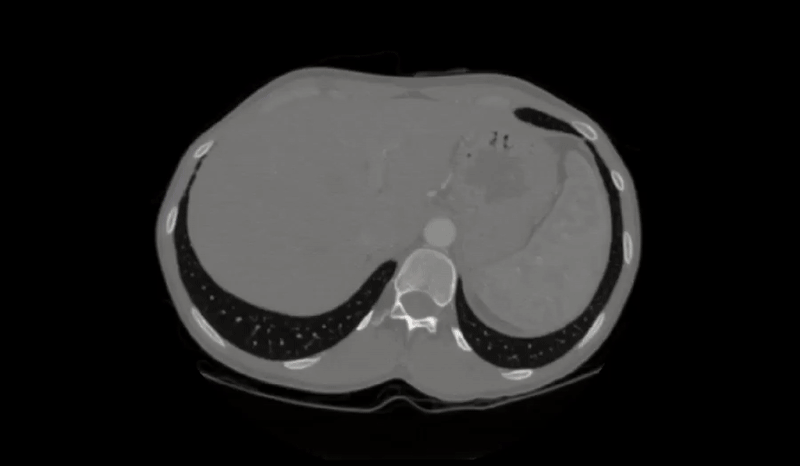

Abdomen Organ Detection

Abdomen Segmentation from TransUNet

As the name suggests, this problem relies on segmenting various organs within the abdomen. It often tackles the modality of CT scans and segments organs across multiple slices.

Level Tracing allows you to autoselect a group of voxels based on the Hounsfield units of the selected voxel with adjustable tolerance.

This feature can be incredibly useful in medical image analysis, especially for tasks like isolating specific tissues or structures within a CT scan. For example, it might be used to automatically select and segment all the soft tissue within a certain range of Hounsfield Units while excluding bone or air. The adjustable tolerance allows radiologists or researchers to adapt the selection to their specific needs, improving the efficiency and accuracy of their analysis.